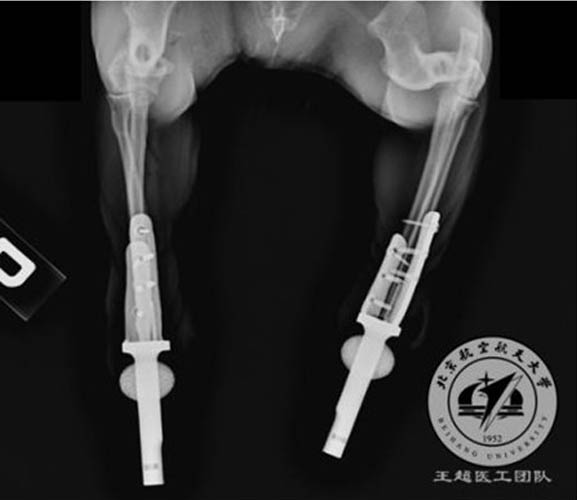

Earlier, Eplus3D cooperated with a medical professionals team guided by Dr. Wang Chao from Beijing Advanced Innovation Center for Biomedical Engineering of Beihang University decided to help the cat to walk normally again by applying titanium prosthetic limbs. These limbs were printed by Eplus3D metal 3D printer as 3D printing can realize complicated shape and precise deign of internal structure through customization. Meantime, loose structure can insure long-term stability. Together with the biological compatibility of titanium material, 3D-printed prosthetic limbs will be with more proper strength and hardness, which can meet biological skeleton properties and can help cat to recover in a faster way.

Little Cat Walks Again with the Help of Eplus3D Metal 3D Printers.